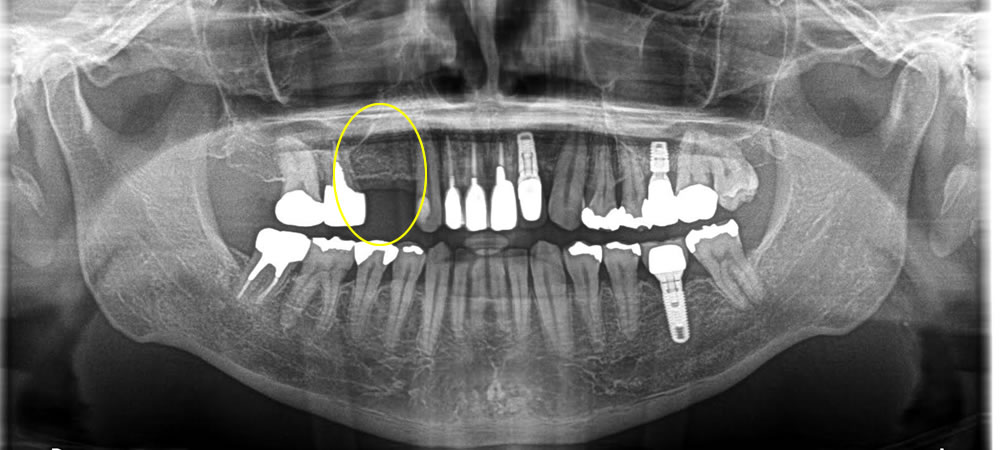

欠損部にインプラントを埋入して咬み合わせを回復した症例

こちらの患者さまは歯の無いところにインプラント治療を行いたいとの事でご来院されました。

カウンセリングの後CT検査にて骨がある事を確認し、オペを行っていきました。